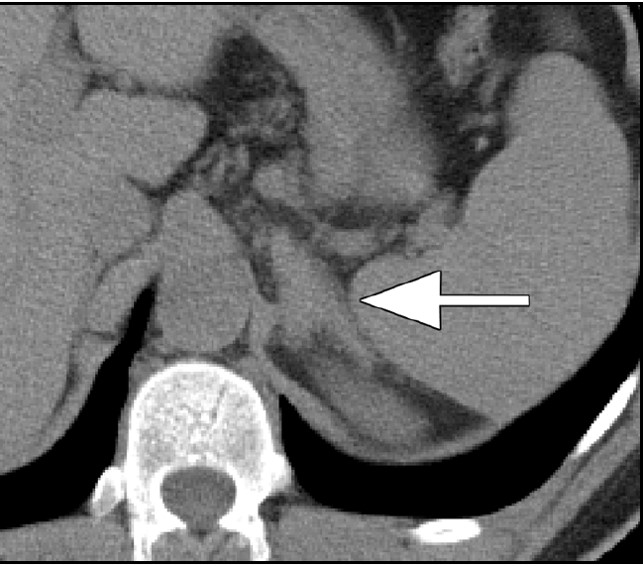

- 【3週間後 MRI 脂肪抑制T1WI】

- 右副腎脂肪抑制T1WIで高信号となっており副腎出血を疑う。

- 左副腎の腫大は改善